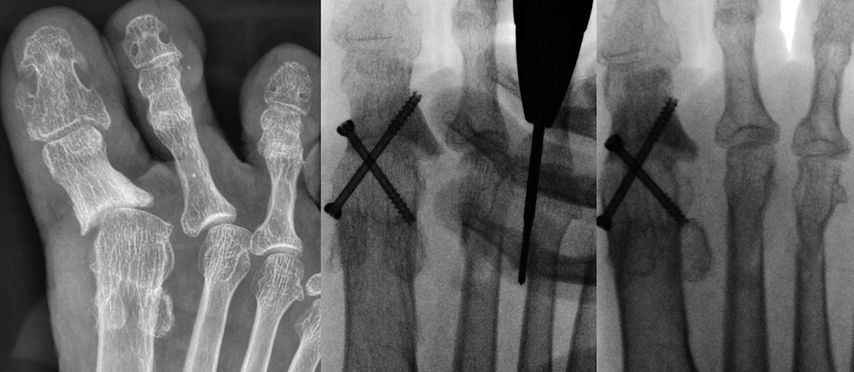

Eine Hammerzehe oder auch mediale bzw. laterale Deviation kann mit perkutan durchgeführten Osteotomien mit der minimalinvasiven Fräse korrigiert werden. Bei einer Hammerzehenfehlstellung erfolgt nach Stichinzision unter der Basis der Grundphalanx bzw. dorsal an der Mittelphalanx, nach Abschieben der Weichteile mittels Elevatorium, mit der Fräse eine Kortikotomie unter Erhaltung der gegenüberliegenden Kortikalis. Dann kann durch Druck die Osteotomie geschlossen und damit die Korrektur erzielt werden. Falls über dem PIP-Gelenk noch eine Prominenz tastbar ist, wird diese über die dorsale Inzision mit der Fräse abgeschliffen.21,22

Isolierte Überlängen von Zehen können mit minimalinvasiven Osteotomien an der Grundphalanx sehr gut korrigiert werden (Abb. 6). Bei Fehlstellungen in der Transversalebene wird ebenfalls über eine Stichinzision in Höhe der Fehlstellung eine Kortikotomie durchgeführt und die Fehlstellung durch Schließen der Osteotomie korrigiert (Abb. 7).

Die Nachbehandlung erfolgt mit Tape-Zügeln im postoperativen Schuh.